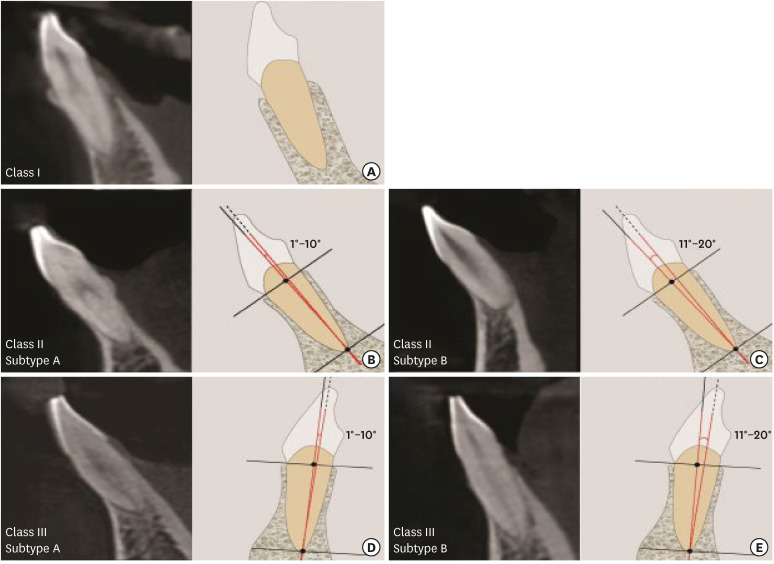

Results: FAB1 and LAB1 were predominantly thin (<1 mm) (84.4% and 73.4%, respectively), with the lateral incisors being thinnest. At the apical level, FAB2 and LAB2 were thick in 99.5% and 99.1% of cases, respectively. Significant differences were documented in FAB2 (P=0.004), LAB1 (P=0.001), and LAB2 (P=0.001) of all mandibular teeth. At all apical levels of the inspected teeth, a significant negative correlation existed between TA and FAB2. Meanwhile, TA showed a significant positive correlation with LAB2 of the lateral incisors and canines. These patterns were then divided into class I (thick facial and lingual alveolar bone), class II (facially inclined teeth) with subtype A (1°-10°) and subtype B (11°-20°), and class III (lingually inclined teeth) with subtype A (1°-10°) and subtype B (11°-20°).

Conclusions: Mandibular anterior teeth have predominantly thin facial and lingual crests, making the lingual bone apical thickness crucial for IIP. Although anchorage can be obtained from lingual bone, tooth angulation and tooth types had an impact on IIP planning. Hence, the new classification based on TA and alveolar bone wall may enable rational clinical planning for IIP treatment.